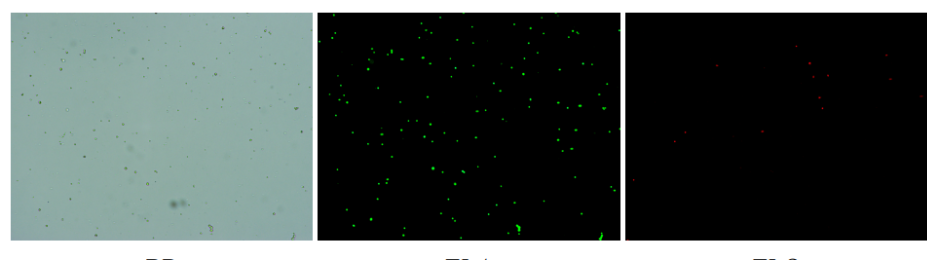

實驗結(jié)果

人膽管癌樣本,活性90.45%,結(jié)團(tuán)率7.2%